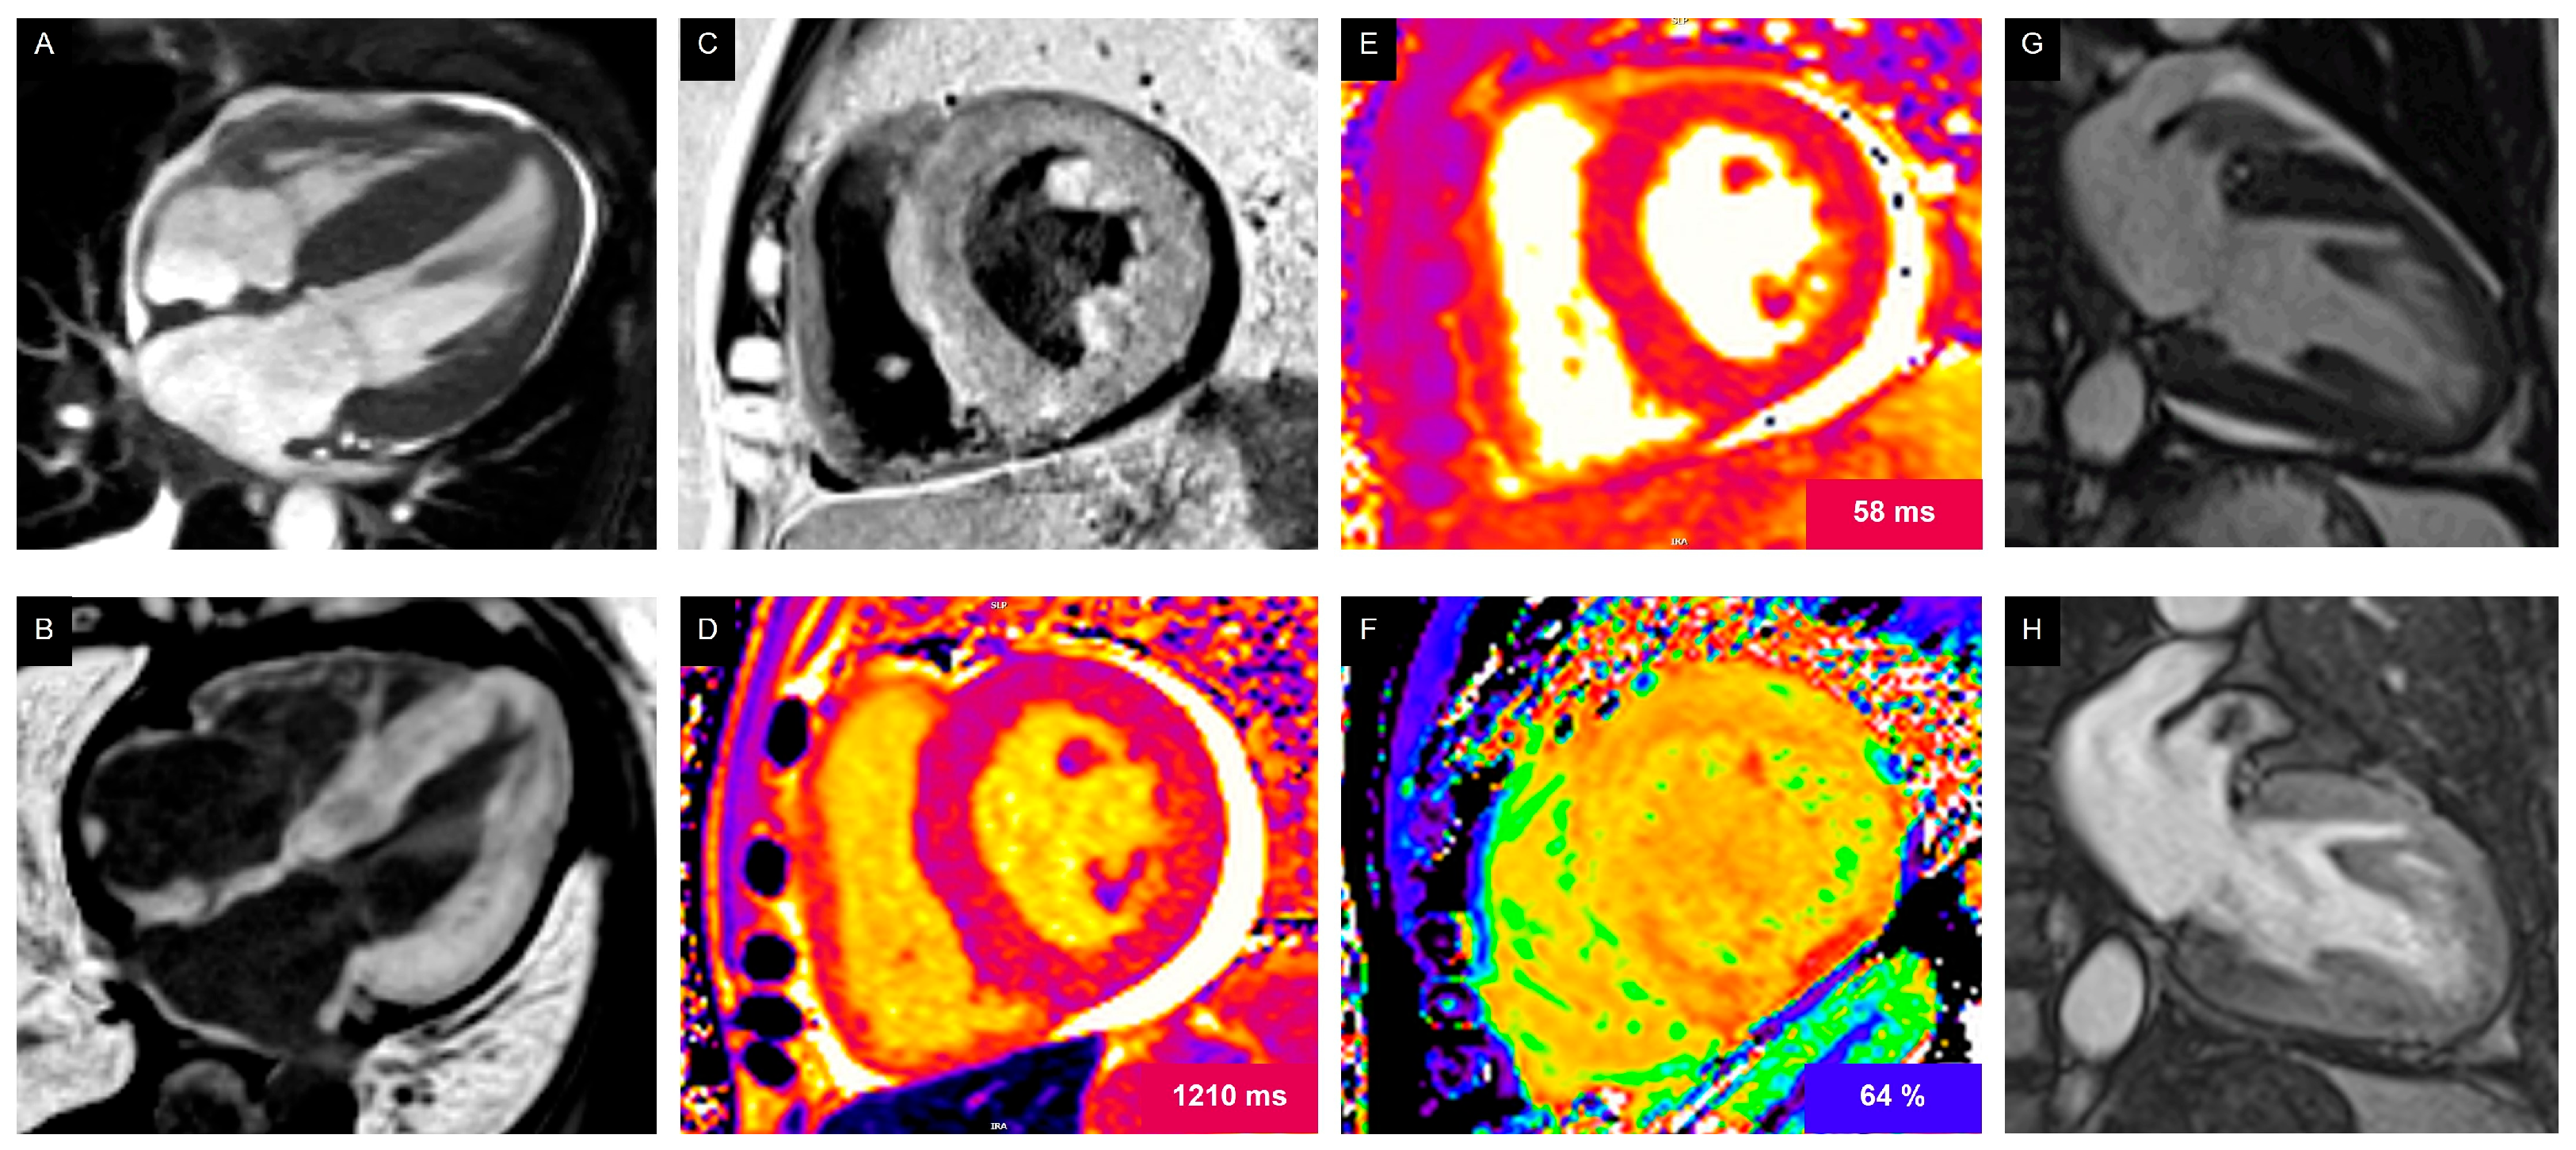

- Thavendiranathan, P.; Zhang, L.; Zafar, A.; Drobni, Z.D.; Mahmood, S.S.; Cabral, M.; Awadalla, M.; Nohria, A.; Zlotoff, D.A.; Thuny, F.; et al. Myocardial T1 and T2 Mapping by Magnetic Resonance in Patients With Immune Checkpoint Inhibitor–Associated Myocarditis. J. Am. Coll. Cardiol. 2021, 77, 1503–1516. [Google Scholar] [CrossRef]

- Messroghli, D.R.; Moon, J.C.; Ferreira, V.M.; Grosse-Wortmann, L.; He, T.; Kellman, P.; Mascherbauer, J.; Nezafat, R.; Salerno, M.; Schelbert, E.B.; et al. Clinical Recommendations for Cardiovascular Magnetic Resonance Mapping of T1, T2, T2* and Extracellular Volume: A Consensus Statement by the Society for Cardiovascular Magnetic Resonance (SCMR) Endorsed by the European Association for Cardiovascular Imaging (EACVI). J. Cardiovasc. Magn. Reson. 2016, 19, 75. [Google Scholar] [CrossRef] [PubMed]

- Ferreira, V.M.; Schulz-Menger, J.; Holmvang, G.; Kramer, C.M.; Carbone, I.; Sechtem, U.; Kindermann, I.; Gutberlet, M.; Cooper, L.T.; Liu, P.; et al. Cardiovascular Magnetic Resonance in Nonischemic Myocardial Inflammation. J. Am. Coll. Cardiol. 2018, 72, 3158–3176. [Google Scholar] [CrossRef]

- Burrage, M.K.; Ferreira, V.M. The Use of Cardiovascular Magnetic Resonance as an Early Non-Invasive Biomarker for Cardiotoxicity in Cardio-Oncology. Cardiovasc. Diagn. Ther. 2020, 10, 610–624. [Google Scholar] [CrossRef]

- Thavendiranathan, P.; Wintersperger, B.J.; Flamm, S.D.; Marwick, T.H. Cardiac MRI in the Assessment of Cardiac Injury and Toxicity From Cancer Chemotherapy. Circ. Cardiovasc. Imaging 2013, 6, 1080–1091. [Google Scholar] [CrossRef]

- Thavendiranathan, P.; Amir, E.; Bedard, P.; Crean, A.; Paul, N.; Nguyen, E.T.; Wintersperger, B.J. Regional Myocardial Edema Detected by T2 Mapping Is a Feature of Cardiotoxicity in Breast Cancer Patients Receiving Sequential Therapy with Anthracyclines and Trastuzumab. J. Cardiovasc. Magn. Reson. 2014, 16, P273. [Google Scholar] [CrossRef]

- Kramer, C.M.; Hanson, C.A. CMR Parametric Mapping in Immune Checkpoint Inhibitor Myocarditis. J. Am. Coll. Cardiol. 2021, 77, 1517–1519. [Google Scholar] [CrossRef] [PubMed]